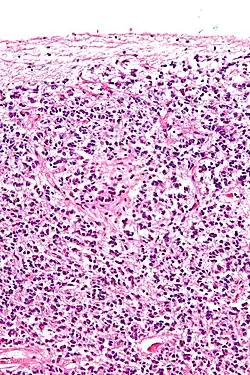

Sección transversal de los pinealocitos presentes en la glándula pineal y en otras células

Los pinealocitos de Tipo 1 son también conocidos como los pinealocitos de la luz, ya que se tiñen a una densidad muy baja cuando se observan bajo la luz de un microscopio y aparecen más claros para el ojo humano. Estas células de Tipo 1 han sido identificadas por tener una forma oval o redonda y un diámetro que oscila entre los 7 y 11 micrómetros. Los pinealocitos de Tipo 1 suelen ser más numerosos tanto en niños como en adultos que los pinealocitos de Tipo 2. También están consideradas por ser las células más activas debido a la presencia de ciertos contenidos celulares, incluyendo una elevada concentración mitocondrial. Otro hallazgo consistente en los pinealocitos de Tipo 1 es el incremento en la tasa de lisosomas y gránulos densos presentes en las células conforme la edad del organismo se va incrementando, indicando posiblemente la importancia de la autofagocitosis en estas células. Investigaciones también han revelado que los pinealocitos de Tipo 1 contienen el neurotransmisor serotonina, que subsecuentemente es convertido en melatonina, la principal hormona secretada por la glándula pineal.

Los pinealocitos de Tipo 2, también conocidos como pinealocitos de la oscuridad, ya que se tiñen a una elevada densidad cuando se observan bajo la luz de un microscopio y aparecen más oscuros para el ojo humano. Como indican diversas investigaciones en microcopia, son células alargadas de forma oval o redonda con diámetro aproximado de entre 7 y 11.2 micrómetros. El núcleo de los pinealocitos de Tipo 2 contiene muchos repliegues que albergan grandes cantidades de ribosomas y de retículo endoplasmático rugoso. Una abundancia de cilios y de centriolos se han encontrado también en estas células de Tipo 2 de la glándula pineal. Solamente en el Tipo 2 está la presencia de vacuolas que alberga 2 capas de membrana. Como las células de Tipo 1 que contienen serotonina, las células de Tipo 2 albergan melatonina y se cree que tienen características similares a las células endocrinas y neuronales.